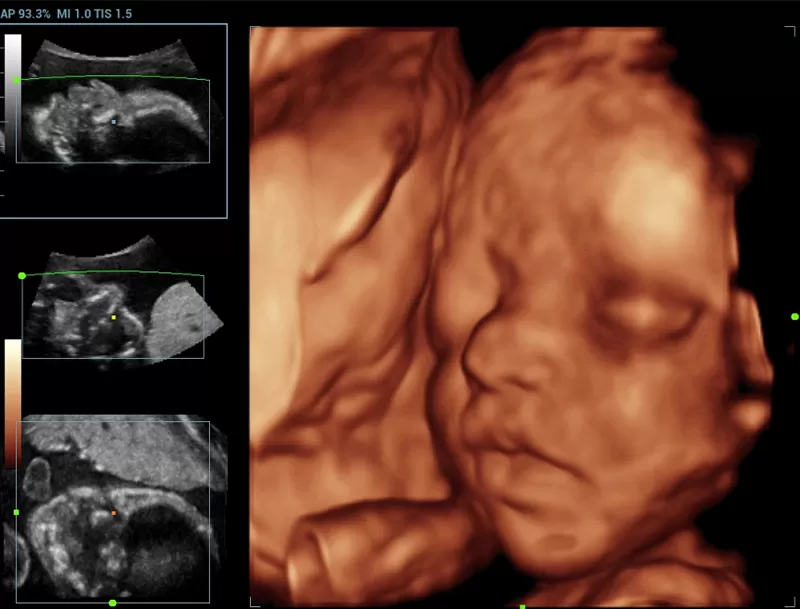

Στη διάθεση σας θα βρίσκονται καταρτισμένοι συνεργάτες μας οι οποίοι θα αναλάβουν να σας παρουσιάσουν τις δυνατότητες του Premium υπερηχογράφου Resona που αποτελεί μια πραγματικά επαναστατική πλατφόρμα, με δεκαπλάσια ταχύτητα σάρωσης χάρις στη μοναδική τεχνολογία zone sonography technology ZST+ που διαθέτει.

Η σειρά Resona ξεχωρίζει όχι μόνο για την κορυφαία απεικονιστική της τεχνολογία αλλά και για τα ευέλικτα εργαλεία ανάλυσης, προσφέροντας ποιότητα απεικόνισης υψηλού επιπέδου και αυξημένη διαγνωστική ακρίβεια.

- New iLive with Hyaline

- Smart Face